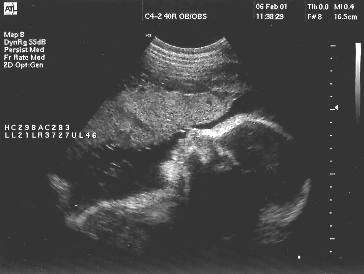

وهذه صور أجنة توأم عبر جهاز موجات فوق الصوتية :